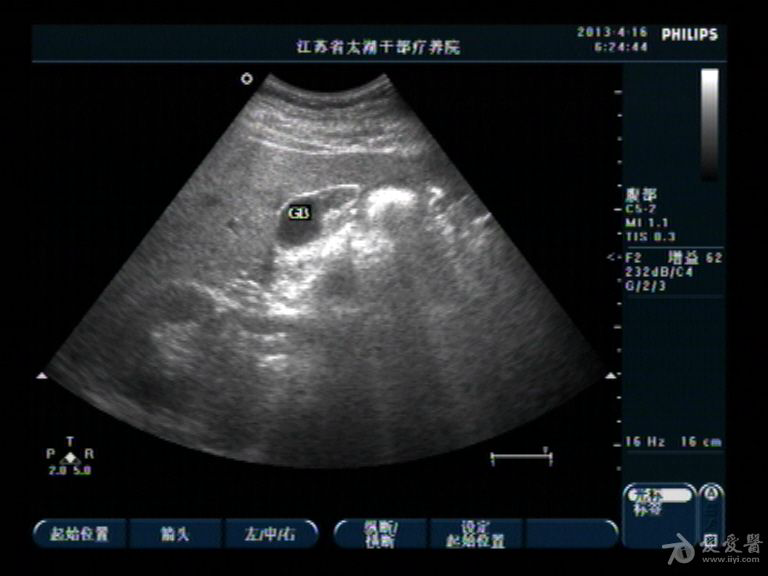

胆囊底部稍低回声区,胆泥沉积?胆囊癌不像吧?,请分析

男性,40,无右上腹痛